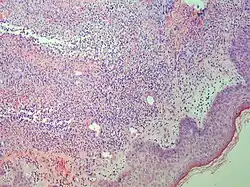

| Lichen planus | Irregular epidermal hyperplasia with a jagged “sawtooth” appearance, compact hyperkeratosis or orthokeratosis, foci of wedge-shaped hypergranulosis, basilar vacuolar degeneration, slight spongiosis in the spinous layer, and squamatization. The dermal papillae between the elongated rete ridges are frequently dome shaped. Necrotic keratinocytes can be observed in the basal layer of the epidermis and at the dermal-epidermal junction. Eosinophilic remnants of anucleate apoptotic basal cells may also be found in the dermis and are referred to as “colloid or civatte bodies”. Whickham striae are usually seen in the areas of hypergranulosis. Vacuolar degeneration at the basal layer may be noted leading to focal subepidermal clefts (Max Joseph spaces). Squamatization occurs as a result of maturation and flattening of cells in the basal layer. It happens in areas of marked hypergranulosis with prominence of the sawtooth pattern of rete ridges. Wedge-shaped hypergranulosis can occur in the eccrine ducts (acrosyringia) or hair follicles (acrotrichia). In the hypertrophic subtype, the associated hyperkeratosis, parakeratosis, hypergranulosis, papillomatosis, acanthosis, and hyperplasia markedly increased with thicker collagen bundles forming in the dermis. Moreover, the rete ridges are more elongated and rounded as opposed to the typical sawtooth pattern. In atrophic LP, loss of the rete ridges and dermal fibrosis is prominent. In vesiculobullous LP, the disease progression is quicker. Hence, some of the distinctive features such as hyperkeratosis, hypergranulosis, or dense lymphocytic dermal-epidermal infiltrate may not be present. LP lesion may resolve with residual hyperpigmentation caused by a persistent increase in the number of melanophages in the papillary dermis.[9] | ![]() |